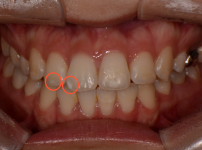

화이트스팟 아이콘레진치료

김OO님/치료기간:1일/화이트스팟 아이콘레진치료   ...